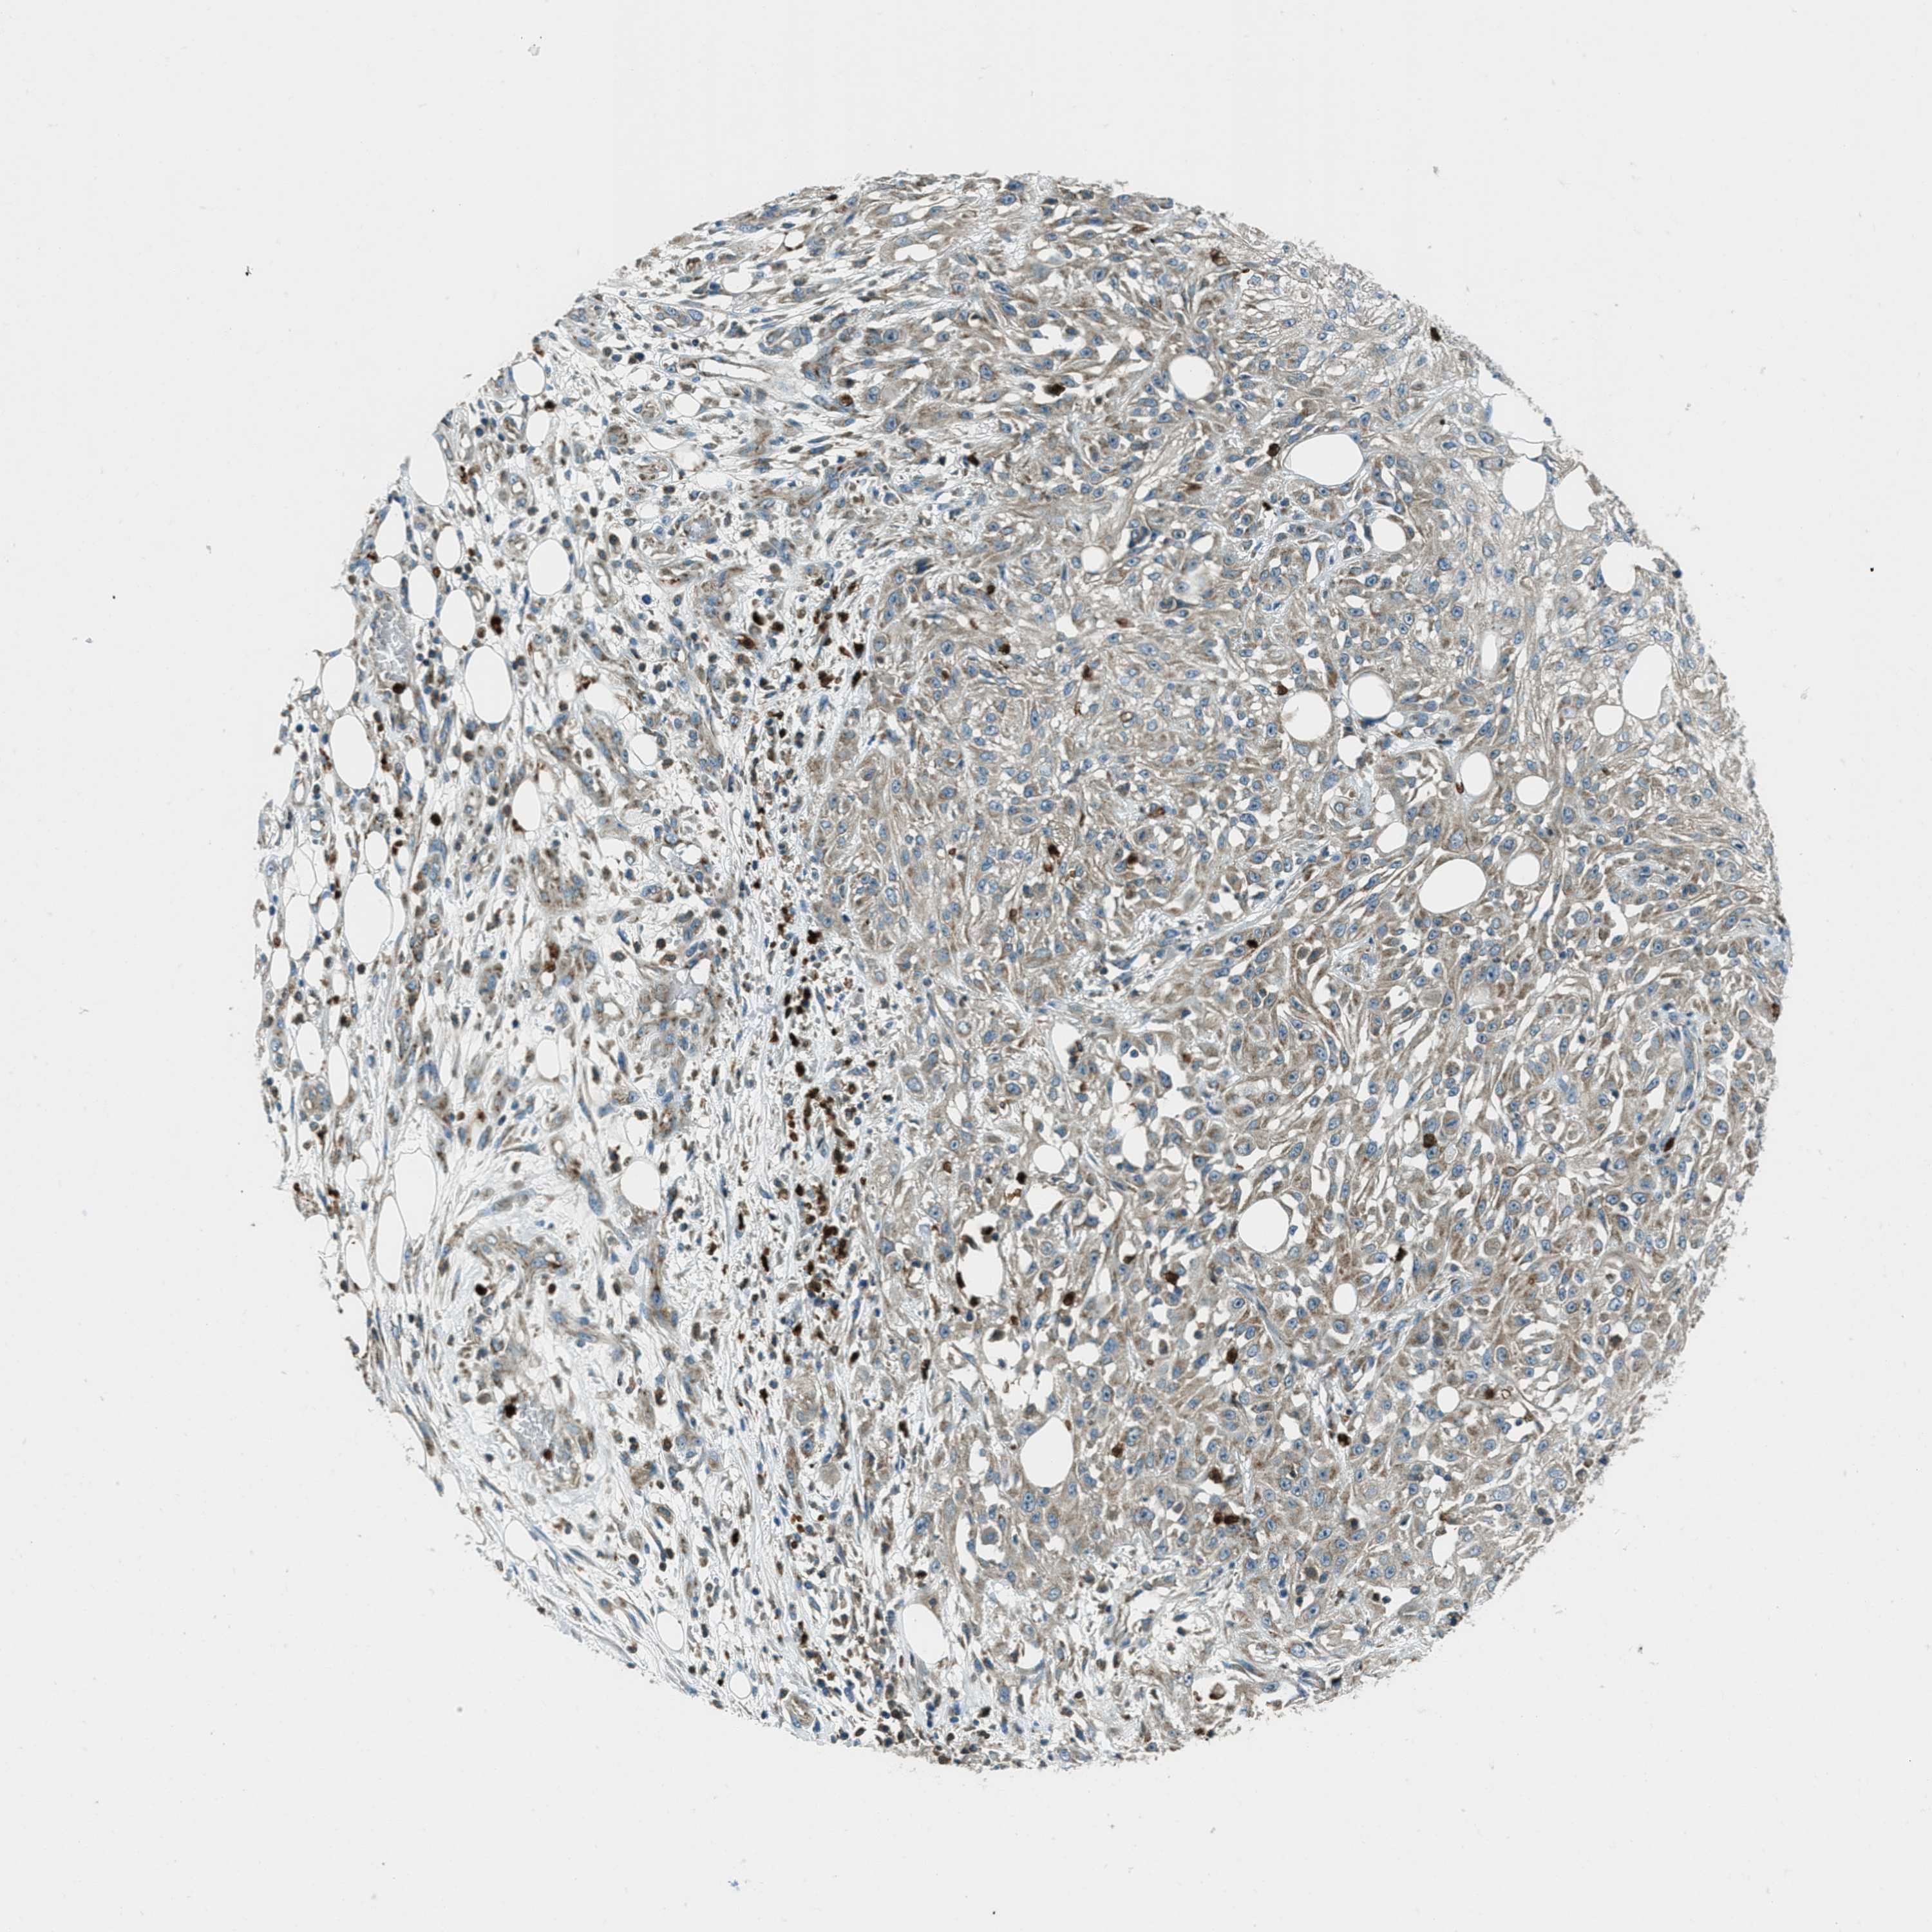

SKIN CANCER - Protein expressioni

A mouse-over function shows sample information and annotation data. Click on an image to view it in a full screen mode. Samples can be filtered based on level of antibody staining by selecting one or several of the following categories: high, medium, low and not detected. The assay and annotation is described here.

Antibody stainingi

Antibody staining in the annotated cell types in the current human tissue is reported as not detected, low, medium, or high, based on conventional immunohistochemistry profiling in selected tissues. This score is based on the combination of the staining intensity and fraction of stained cells.

Each image is clickable and will lead to virtual microscopy that enables deeper exploration of all samples and also displays staining intensity scores, fraction scores and subcellular localization as well as patient and tissue information for each sample.

Antibody HPA017322

Staining

High

Medium

Low

Not detected

Intensity

Strong

Moderate

Weak

Negative

Quantity

>75%

75%-25%

<25%

None

Location

Nuclear

Cytoplasmic/membranous

Cytoplasmic/membranous,nuclear

Squamous cell carcinoma in situ, NOS

Squamous cell carcinoma, NOS

Squamous cell carcinoma, metastatic, NOS

Basal cell carcinoma